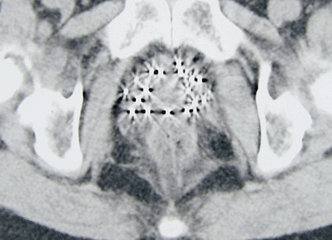

盆腔CT显示粒子分布